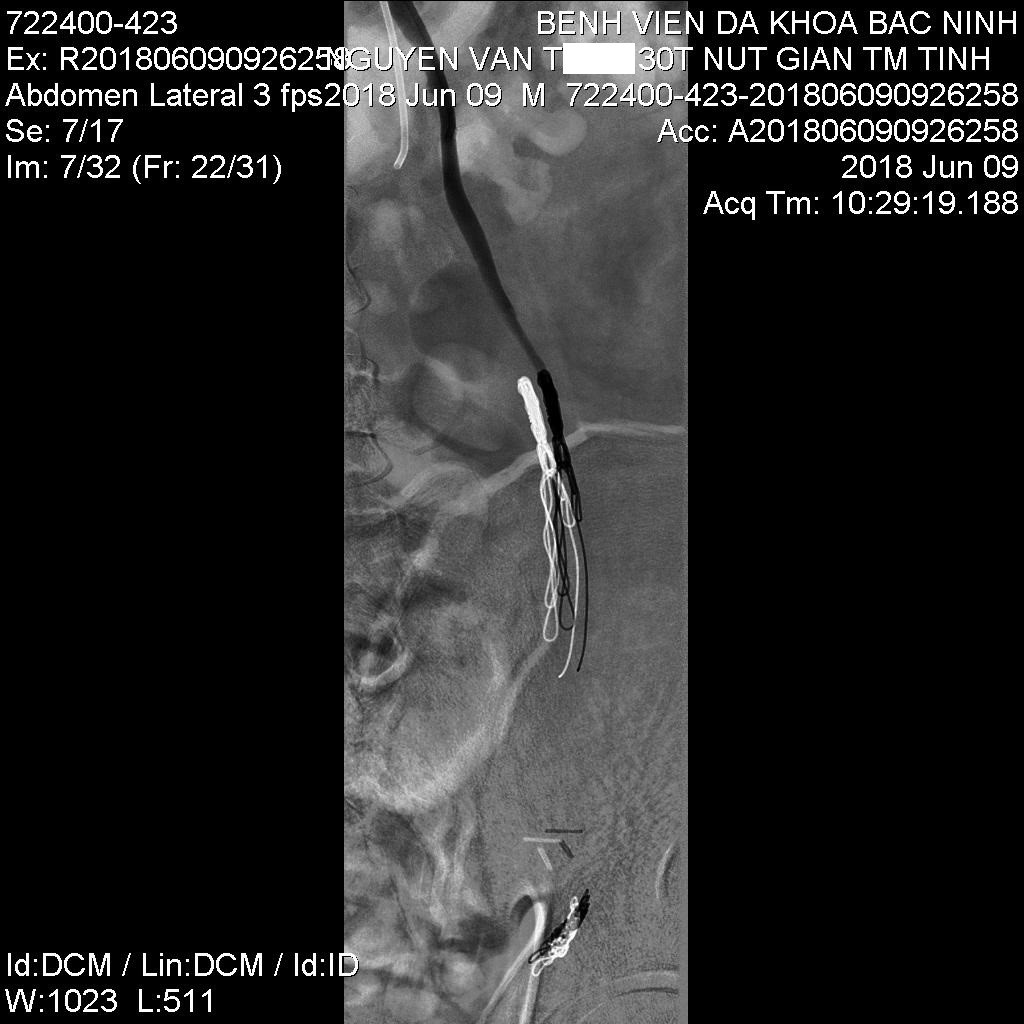

![]() Sau can thiệp |

Kỹ thuật này có nhiều ưu điểm như phương pháp vô cảm gây tê tại chỗ dưới da, bệnh nhân hoàn toàn tỉnh trong quá trình can thiệp. Đây là phương pháp can thiệp xâm lấn tối thiểu vào mạch máu bệnh nhân qua duy nhất một dụng cụ mở đường vào tĩnh mạch rộng khoảng 2mm, thông thường vị trí tiếp cận là tĩnh mạch đùi chung bên phải. Sau đó, bác sỹ can thiệp sẽ luồn các loại ống thông và dây dẫn vào trong tĩnh mạch thận trái và tĩnh mạch tinh trái, chụp hình mạch máu dưới máy số hóa xóa nền để đánh giá hình thái, các loại biến đổi giải phẫu và huyết động học tĩnh mạch tinh trái. Sau khi đánh giá được toàn bộ hình thái và động học của các tĩnh mạch tinh giãn, bác sỹ can thiệp lựa chọn vật liệu nút mạch phù hợp để đảm bảo tắc toàn bộ các nhánh tĩnh mạch tinh trái giãn có dòng trào ngược. Thời gian can thiệp ngắn, trung bình 60 – 90 phút kể từ lúc người bệnh vào phòng can thiệp. Sau can thiệp, các loại ống thông được rút bỏ và băng ép vị trí mở đường vào tĩnh mạch đùi, bệnh nhân có thể đi lại bình thường sau 4 giờ can thiệp, có thể xuất viện 1 ngày sau thiệp.